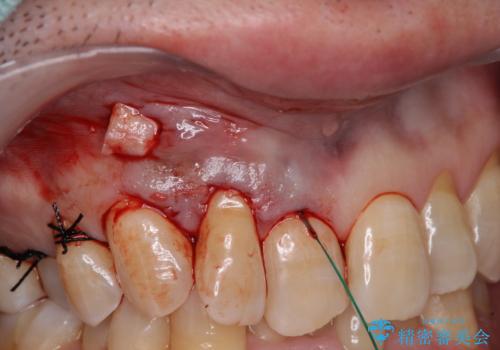

- 強い咬合力による歯肉退縮により、歯の根の黄色い色が見えてしまうことを気にされて来院された患者様です。

口蓋(上顎の内側)から採取した結合組織(歯肉の内側の組織)を移植することによる、根面被覆術を行うこととしました。

ディープバイトで咬合力が強く、該当歯に負担のかかりやすい咬み合わせであったため、歯肉退縮が起こりやすいと判断された患者様でした。

根面被覆を達成するとともに、歯肉の厚みを増すことで、今後歯肉退縮を起こしにくくするよう配慮した処置としました。